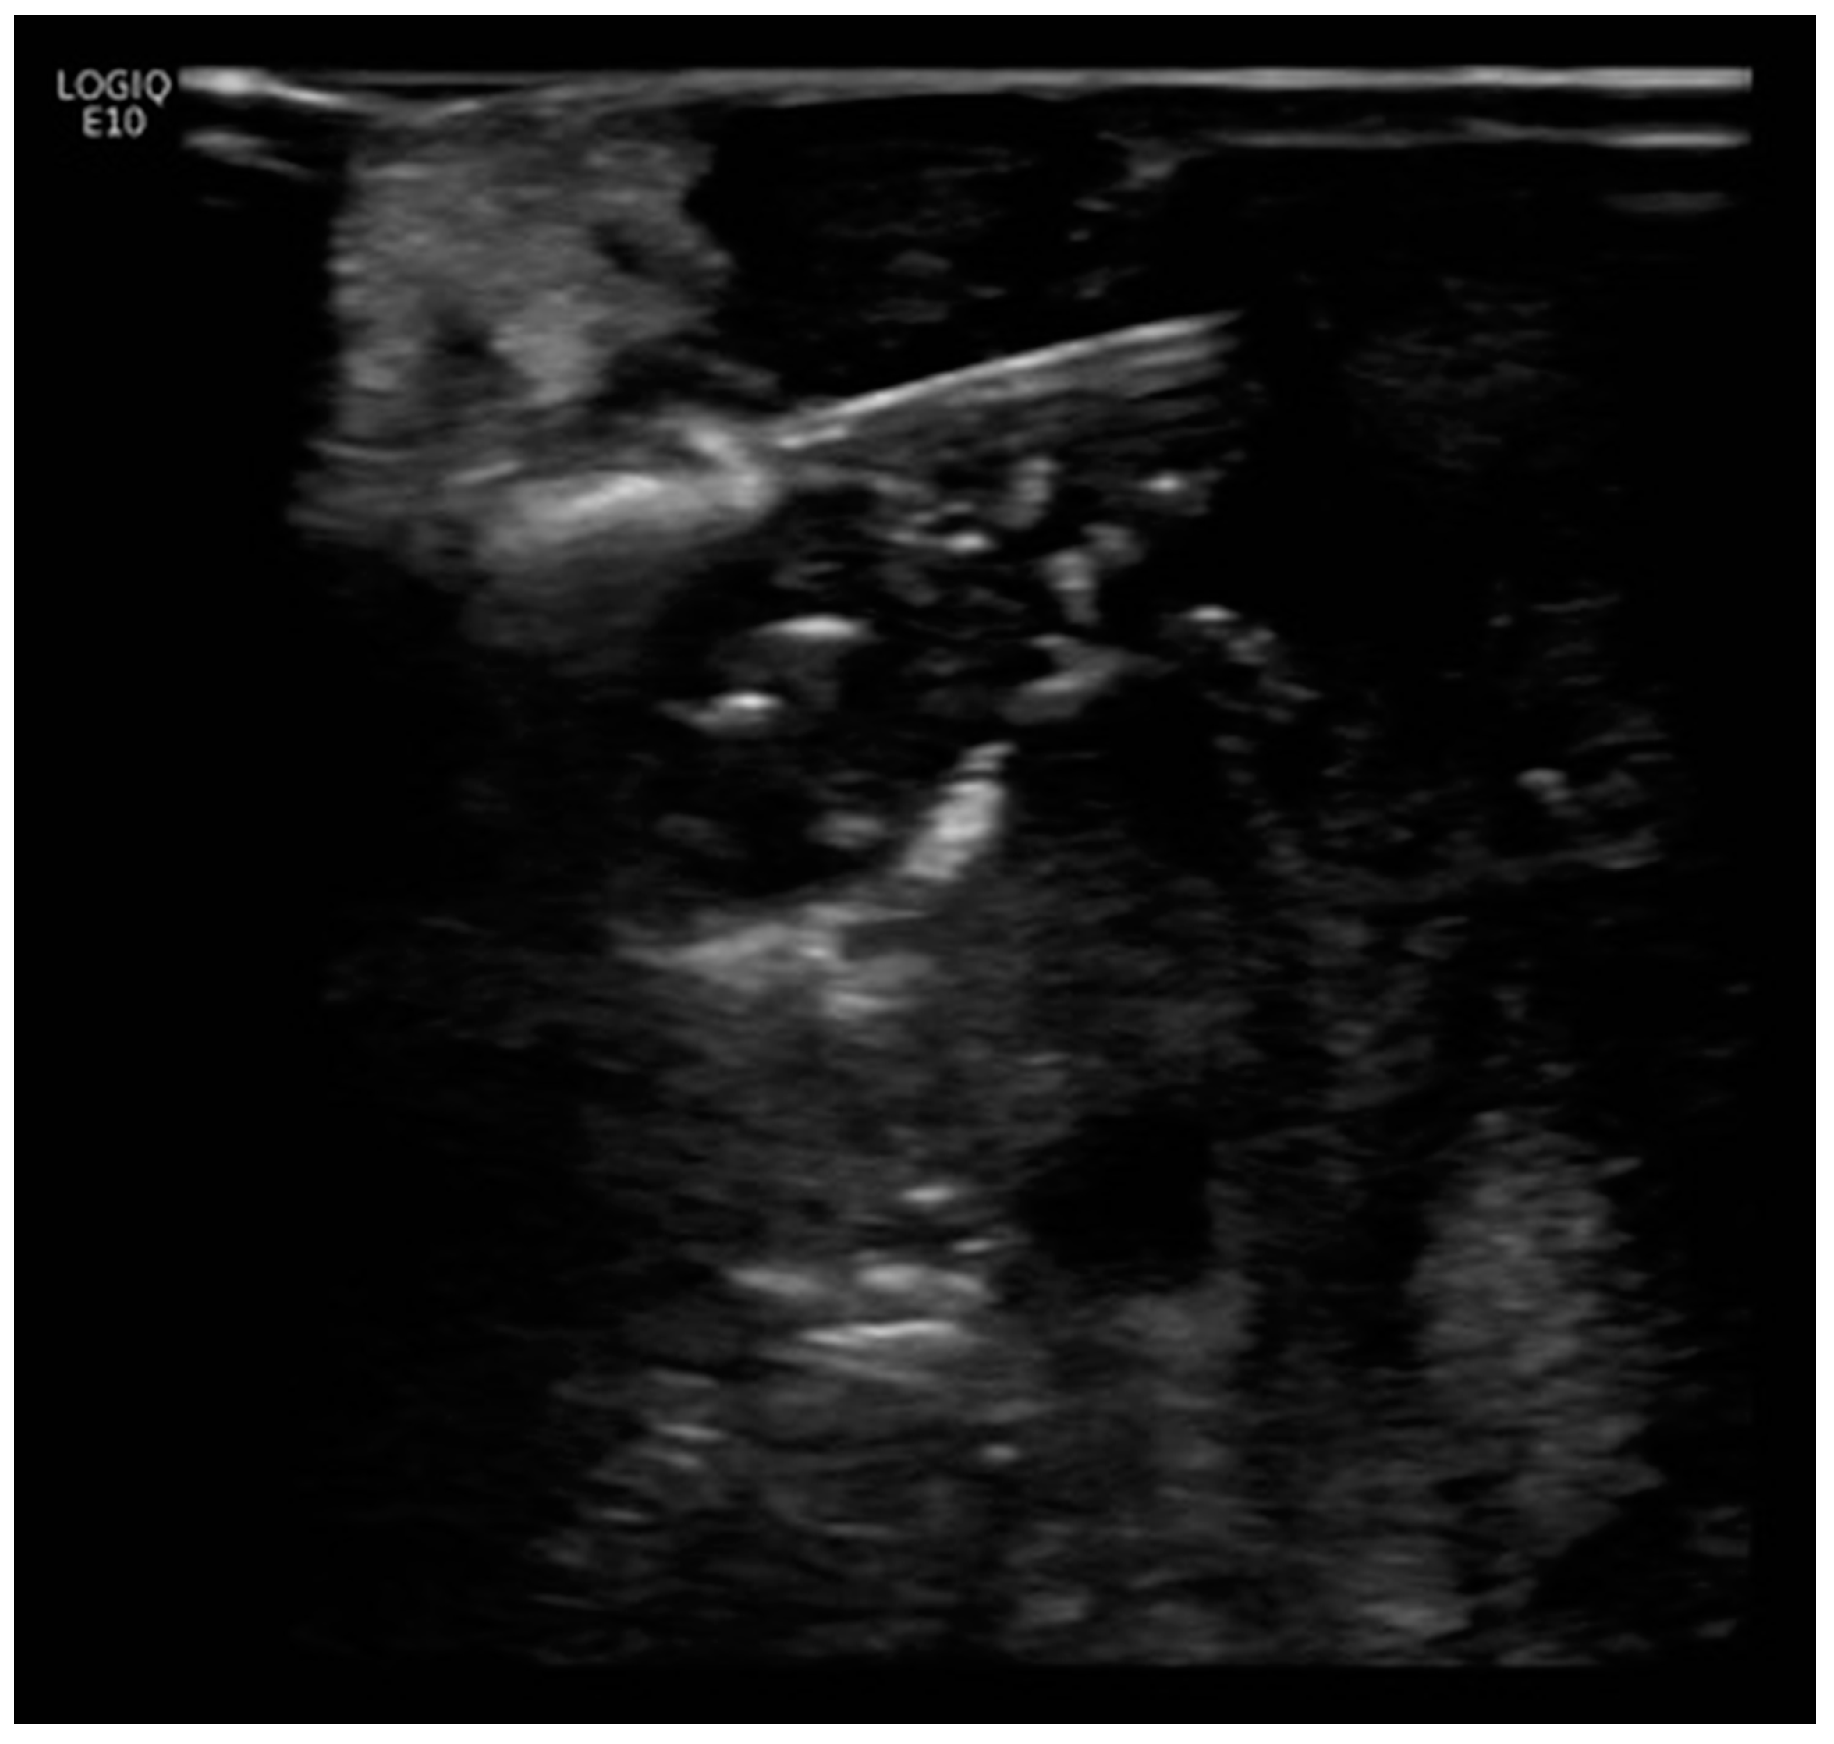

Figure 2.

Intra-operative ultrasound image. Three parallel probe arrays were utilized for open irreversible electroporation (IRE). Open IRE procedural details: Three parallel probe arrays were positioned from medial to lateral, starting from the region besides the superior mesenteric artery. A total of six ablation positions, each with 1 cm tip exposure and five pull backs at each location, was performed. The region besides the duodenal c-loop was avoided to prevent bowel perforation. Ablation using between 80 and 160 pulses at 2000–2500 Volts was delivered at each location (with 12 A rise in current) and monitored under intra-operative ultrasound.